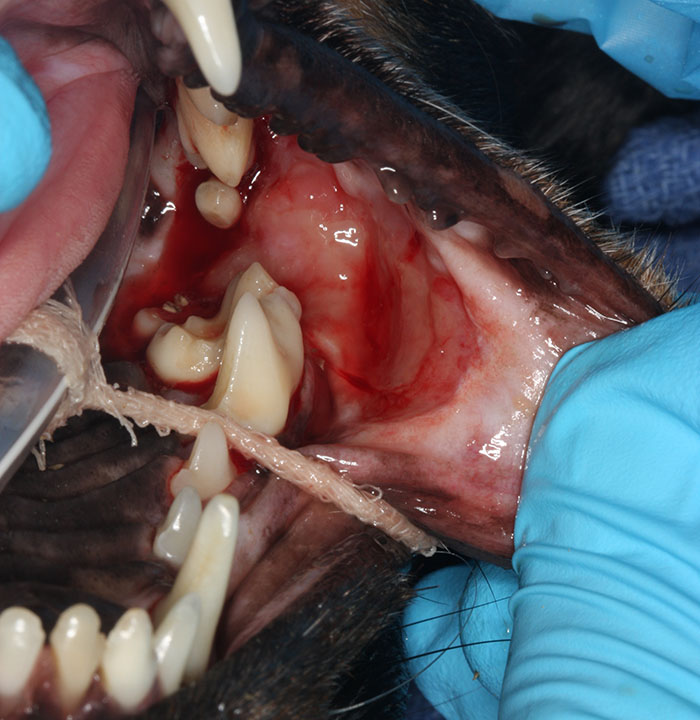

FCGS is an autoimmune condition in which the cat’s immune response to the teeth and/or oral bacteria is abnormally strong. This results in inflammation and pain that can range from mild to severe. The inflammation centers on the back of the mouth, as well as around the teeth, lips and tongue. While there may be an underlying viral trigger, the exact cause is still unknown. Rarely, FCGS can be managed by maintaining a very clean mouth (anesthetized cleanings at regular intervals and daily brushing at home). Oftentimes, however, more aggressive intervention is needed to help your cat stay comfortable.

In the case of severe or generalized inflammation, or when cleanings alone don’t make a difference, sometimes medical management can be successful. In other cases, we need to selectively extract the teeth that are causing problems. While this may be a long-term concern for you and your pet, the North Bay Veterinary Dentistry team will be there for you each step of the way.